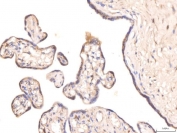

IHC staining of FFPE human placental tissue with KCNQ1 antibody. HIER: boil tissue sections in pH8 EDTA for 20 min and allow to cool before testing.